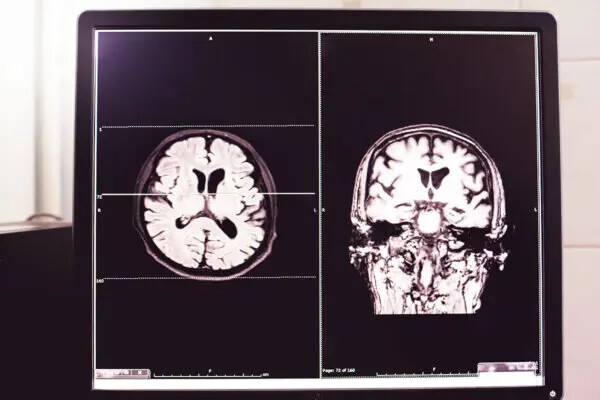

Le Dr Counce s’occupe également de plusieurs patients vaccinés qui ont développé une atrophie cérébrale. L’un d’entre eux présentait une atrophie de l’hippocampe avec des symptômes de perte de mémoire et des changements de personnalité.

Le docteur a pensé que si l’hippocampe, qui sert de centre de mémoire au cerveau, s’atrophie, le système limbique adjacent, qui traite les émotions, pourrait également être affecté de la même manière.